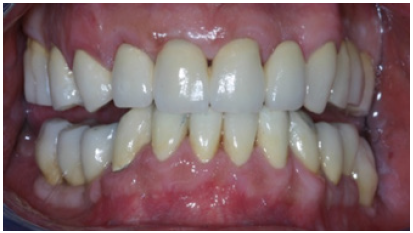

Figure 20: Final restorations after cementation of the all ceramic veneers.

Preparations for veneers, final result

In order to optimize final aesthetics the 5 mandibular anteriors were prepared for all ceramic restorations. Four all ceramic veneers (E-max Ivoclar Co, Liechtenstein) and an all ceramic crown (#42) completed the final restorations. A final occlusal splint was also fabricated chairside (prior to the final cementation of ceramic veneers) for the protection of final restoration and control of TMJ function (Figure 19,20). Minimal occlusal modifications of the splint were necessary after final cementation of mandibular anteriors. The final radiographic examination was kept as a record for future re-examinations (Figure 21). Finally, the patient was enrolled to a 3 months recall program. In each recall and maintenance visit, the periodontal tissues, the abutments and the stomatognathic system were thoroughly examined, preventive regimens were applied and patient compliance was assessed. Two years later, the excellent periodontal condition and performance of the restoration was registrated (Figure 22-24). The patient complied with proper oral hygiene, reduced smoking and adopted a regular use of the occlusal splint. Strict recall and maintenance visits were necessary for long term success of this full mouth rehabilitation. The patient stopped smoking immediately after 6 months and changed nutritional habits in order to eliminate secondary caries.